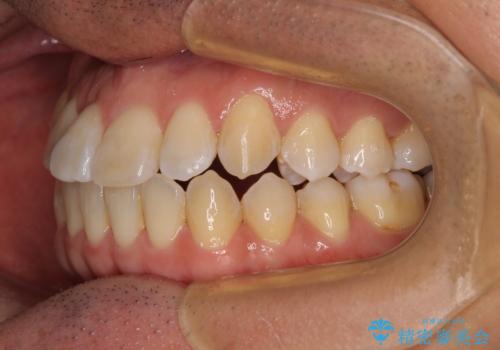

左右の八重歯が気になる ワイヤー装置での咬み合わせ改善

- 治療期間

- 4年1ヶ月

舌の突出癖がなかなか改善されず、上下前歯部の接触が得られるまでに予定の倍ほどの期間がかかりました。